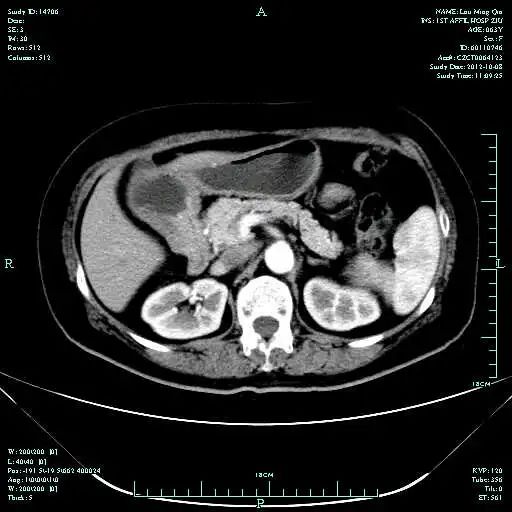

• 第三次FOLFOX+T方案后 B超提示肝转移灶消失

疗效评估:cPR

TOGA研究是第一个使用HER2抑制剂曲妥珠单抗治疗不能手术的局部晚期、复发或转移的HER2阳性胃癌患者的Ⅲ期临床研究。TOGA研究结果显示,IHC2+/FISH阳性或者IHC3+的患者与对照组相比,OS分别为16.0个月和11.8个月(HR为0.65)。曲妥珠单抗联合化疗显著提高了HER2阳性晚期转移性胃癌的治疗缓解率和总体生存率。2012年8月,曲妥珠单抗治疗HER2阳性转移性胃癌适应症在我国获批。对该患者进行病理切片会诊,幸运的是其HER2检测为阳性。随即进行靶向联合化疗治疗,三个周期后,肝转移灶消失,曲妥珠单抗治疗效果显著。九个周期的靶向治疗联合放化疗后,疗效评估cPR,随即行手术治疗。